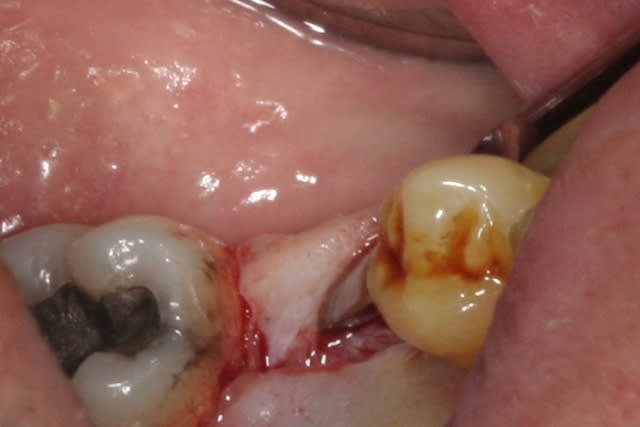

place aux photos!!!

forage, tout ce qu'il y a de plus classique pour ceux qui connaissent ID ou zimmer

pour un implant de 5mm de diamètre on s'arrête au foret de 4.4, passé ici sur 8mm au lieu des 11.5mm car j'étais dans du D3